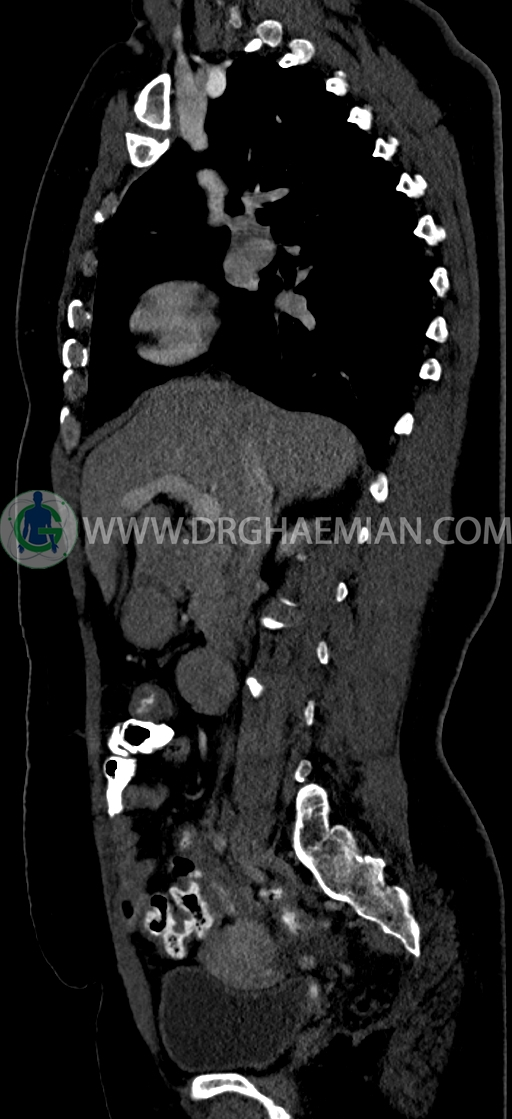

در سي تي اسکن اسپيرال ريه و مدياستن-شکم و لگن با کنتراست خوراکی و وريدی (مولتي ديدکتور 16 با مقاطع ظريف و بازسازي هاي ساژيتال و کرونال) :

-فوليکول به سايز 21mm همراه با مايع آزاد جزئي در لگن مطرح کننده اوولاسيون

-فيبروم اينترامورال- ساب سروزال به سايز 35mm در قدام فوندوس با اثر فشاري بر ديواره فوقاني مثانه

-ضخامت اندومتر حدوداً 20mm ، تطبيق با سونوگرافي واژينال پيشنهاد مي شود.

-هرني سوپرا امبليکال با ديفکت به سايز 10mm حاوي چربي و هرني امبليکال با ديفکت به سايز 7mm حاوي چربي مشهود است.